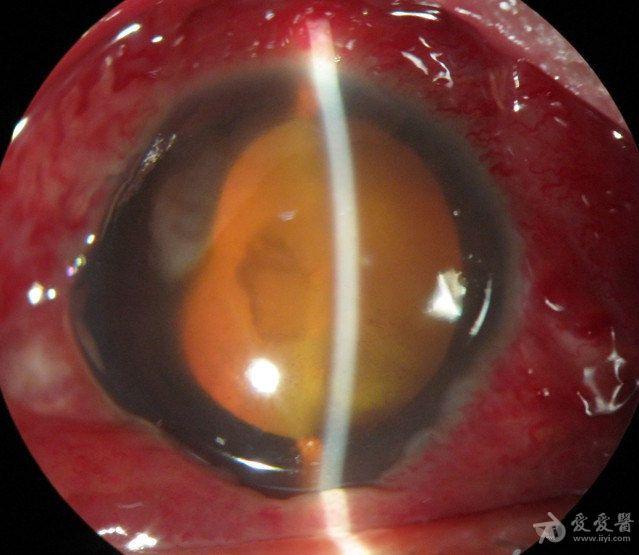

化脓性眼内炎合并眶蜂窝织炎如何治疗?